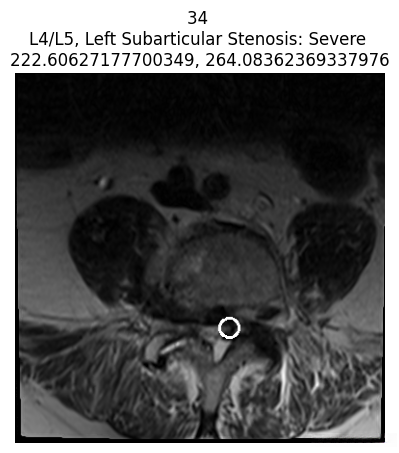

查看病变的坐标

我们还可以显示每位患者标注的病变坐标。

coor_entries = df_coor[df_coor['study_id'] == int(patient['study_id'])]

print("Only showing severe cases for this patient")

for idc, c in coor_entries.iterrows():

for i in im_list_dcm[str(c['series_id'])]['images']:

if int(i['SOPInstanceUID']) == int(c['instance_number']):

try:

patient_severity = patient[

f"{c['condition'].lower().replace(' ', '_')}_{c['level'].lower().replace('/', '_')}"

]

except Exception as e:

patient_severity = "unknown severity"

title = f"{i['SOPInstanceUID']} \n{c['level']}, {c['condition']}: {patient_severity} \n{c['x']}, {c['y']}"

if patient_severity == 'Severe':

display_coor_on_img(c, i, title)

AI写代码

仅显示该患者的严重病例